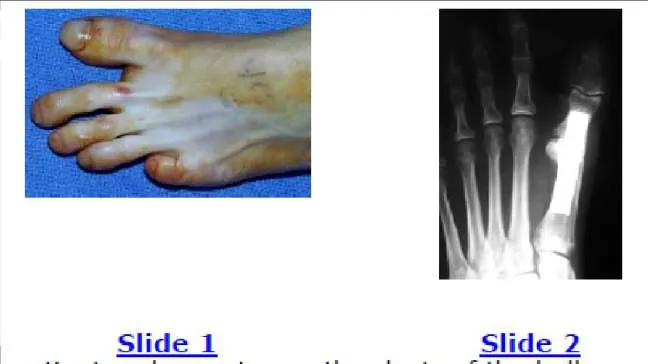

Question 7:

A 52-year-old man presents for treatment of acute pain in the forefoot. He notes that the onset of pain started 24 hours ago, and he is unable to walk. Examination of the hallux (Slide) is uncomfortable. The recommended treatment for this condition is:

Correct Answer: Intra-articular steroid injection

Explanation:

This patient presents with a classic acute gout attack. Although the hallux is in severe valgus, it is unlikely that this is the cause of the joint pain. Note the swelling of the hallux and the shiny skin from the acute inflammation. These clinical findings are typical of gout. Intra-articular injection of steroids is effective treatment and can be combined with oral anti-inflammatory agents.